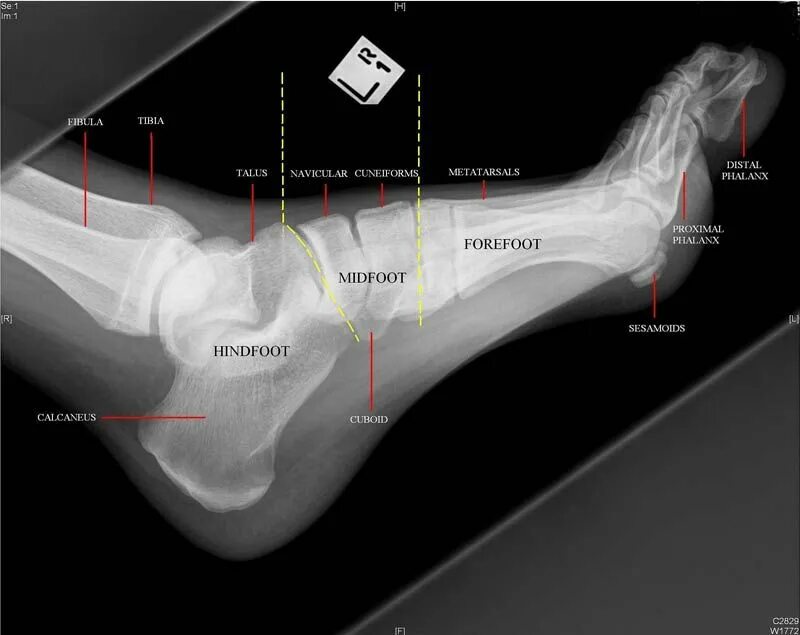

Source x rays